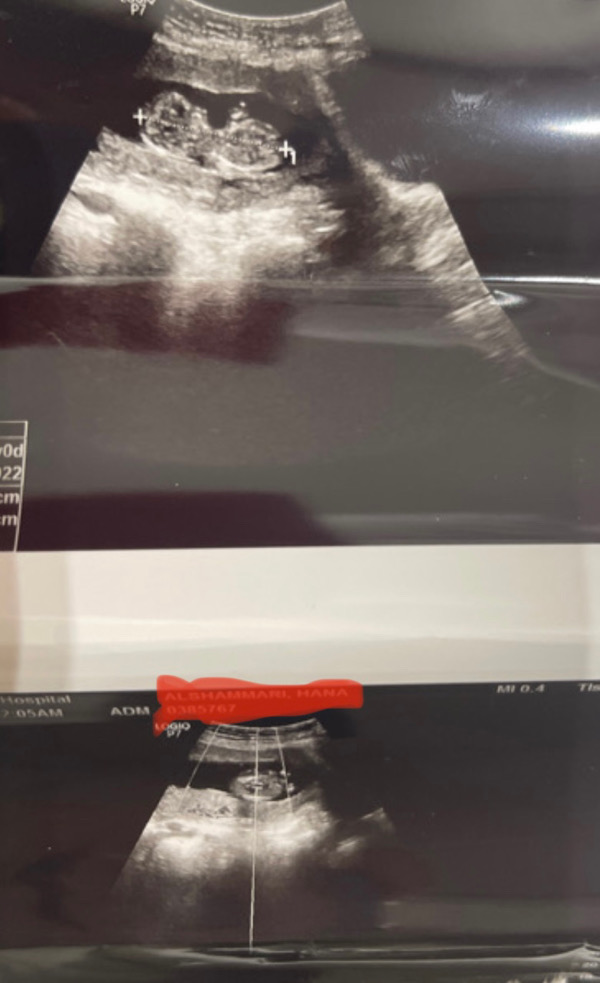

مبروك التجمع الجديد الحمدلله اللهم بارك حامل فى بنت ❤️❤️😍

مبروك البنوته تحضنينها بالسلامه🌸👏🏻